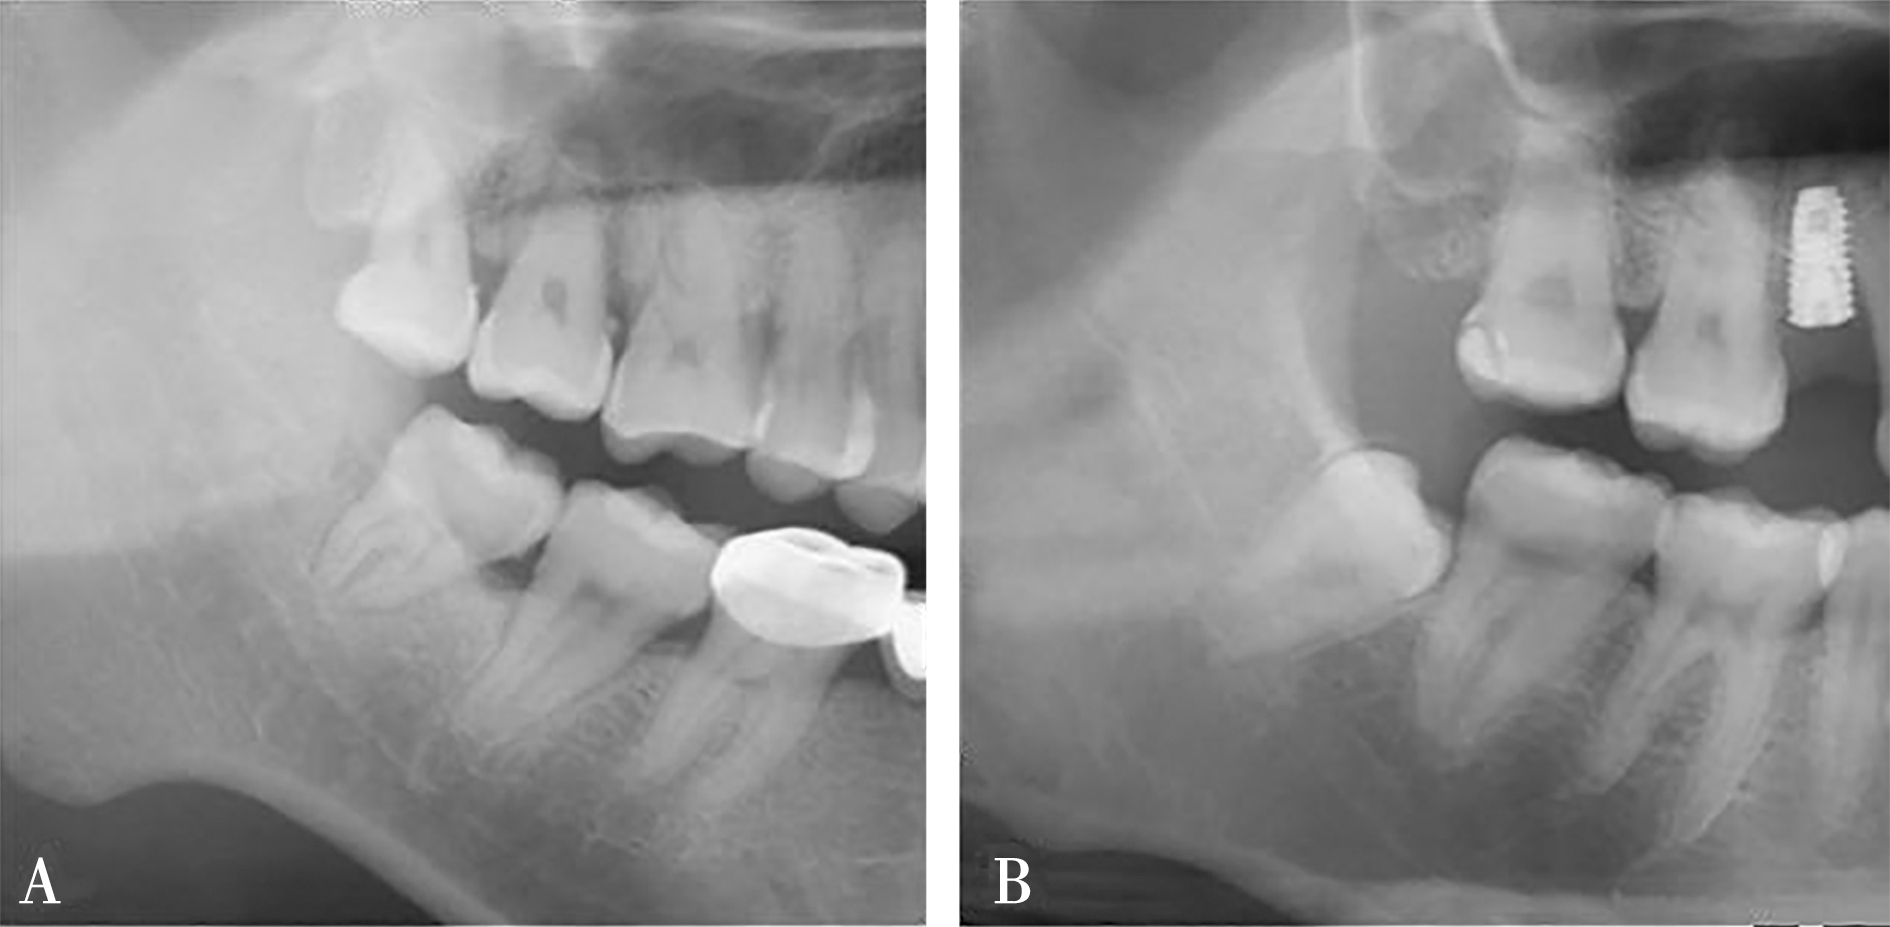

| 下颌管相对M3牙根的位置(CBCT) | 下方 | 816 | (70.77%) | 337 | (29.23%) | <0.000 1* | |

| 颊侧 | 1 173 | (67.92%) | 554 | (32.08%) | |||

| 舌侧 | 101 | (22.15%) | 355 | (77.85%) | |||

| 中间 | 6 | (11.32%) | 47 | (88.68%) | |||

| 下颌管形态(CBCT) | 圆形/卵圆形 | 2 014 | (88.02%) | 274 | (11.98%) | <0.0001* | |

| 狭窄型 | 82 | (7.45%) | 1 019 | (92.55%) | |||